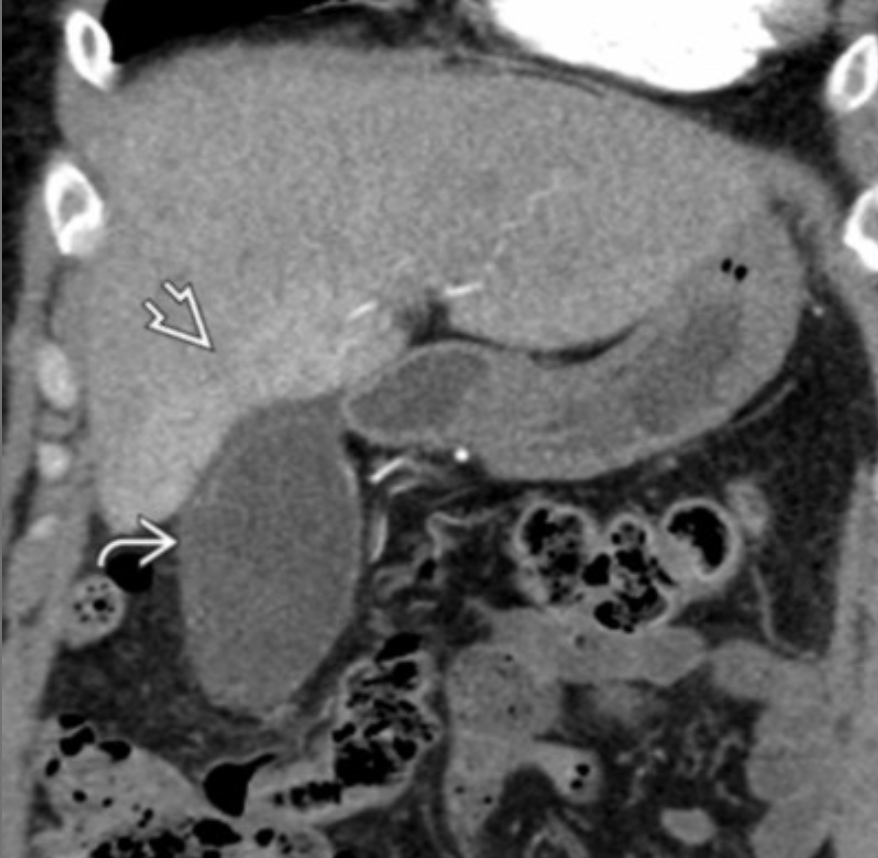

Dx?

Dx: type 4A choledochal cyst.